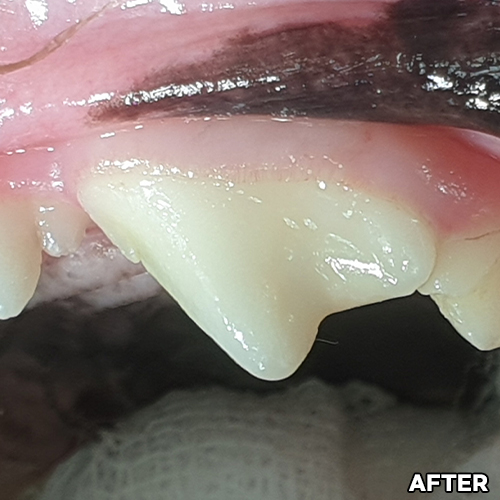

[깨진 강아지 치아 레진치료 전후]